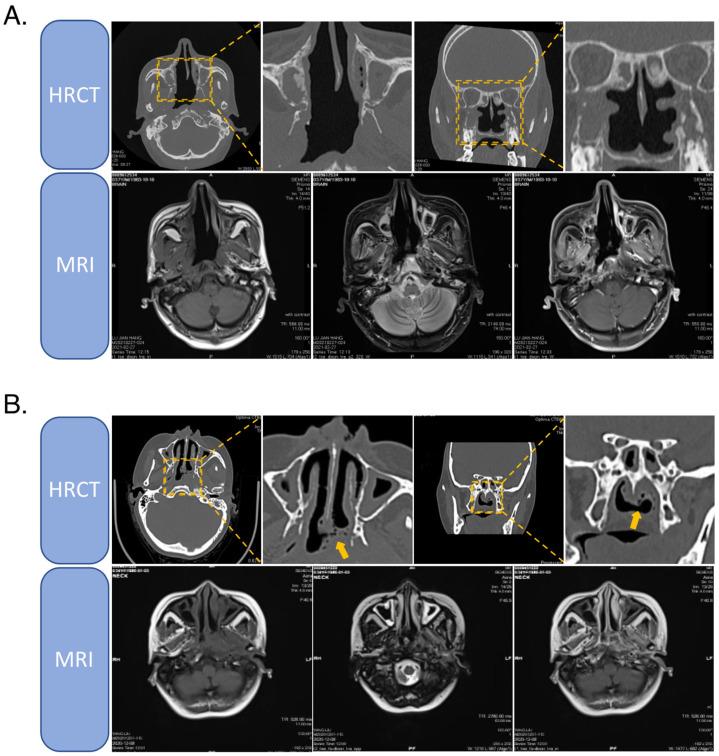

复发性鼻咽癌的治疗:一项序贯性挑战。

Treatment of Recurrent Nasopharyngeal Carcinoma: A Sequential Challenge.

Recurrent nasopharyngeal carcinoma (NPC), which occurs in 10-20% of patients with primary NPC after the initial treatment modality of intensity-modulated radiation therapy (IMRT), is one of the major causes of death among NPC patients. Patients with recurrent disease without distant metastases still have a chance to be saved, but re-treatment often carries more serious toxicities or higher risks. For this group of patients, both otolaryngologists and oncologists are committed to developing more appropriate treatment regimens that can prolong patient survival and improve survival therapy. Currently, there are no international guidelines for the treatment of patients with recurrent NPC. In this article, we summarize past publications on clinical research and mechanistic studies related to recurrent NPC, combined with the experience and lessons learned by our institutional multidisciplinary team in the treatment of recurrent NPC. We propose an objective protocol for the treatment of recurrent NPC.

摘要